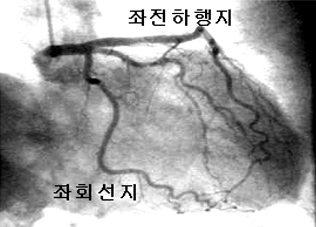

협심증, 심근경색증의 정확한 진단을 위해 운동부하검사, 심근스펙트검사, 심초음파검사, 심장MRI검사, 심장혈관CT 등을 시행하여관상동맥 질환의 유무와 정도를 평가하게 됩니다. 협심증, 심근경색증의 진단이 내려지면 심혈관조영실에서 관상동맥조영술 검사를시행하게 되고 관상동맥의 좁아진 부위와 동맥경화의 중증도에 따라 관상동맥중재술 (관상동맥 풍선확장술 및 스텐트삽입)을 시행하거나수술적인 치료로 관상동맥우회로술을 시행하게 됩니다.

심혈관조영술1 심혈관조영술2

<심혈관조영술1> <심혈관조영술2>